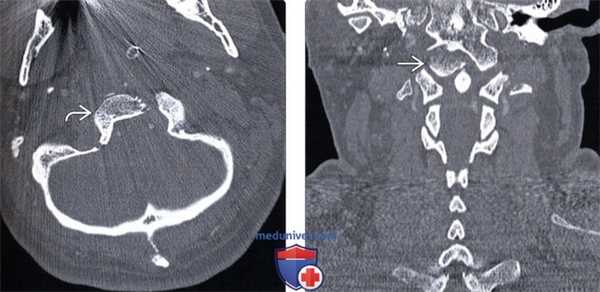

(Справа) На сагиттальном STIR МР-И определяется патологическое расширение и усиление сигнала суставных щелей сочленений С0-С1 и С1-С2. Этому пациенту по поводу атланто-затылочной и атланто-аксиальной диссоциации был выполнен задний спондилодез протяженностью от затылочной кости до СЗ позвонка. (Слева) КТ, аксиальной срез: множественные переломы кольца С1 без признаков компрессии спинномозгового канала.

(Справа) КТ, аксиальной срез: переломы передней и задней дуг С1 в сочетании с отрывом костного фрагмента на уровне прикрепления поперечной связки атланта.